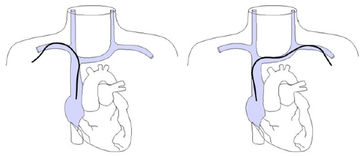

Von links eingeführte Katheter stoßen in der in mehreren Ebenen gewundenen Vena brachiocephalica an die Venenwand an und verursachen Intimaläsionen und Thrombosen. Die Wandschäden sind umso schlimmer, je steifer der Katheter ist. Die schlimmsten Schäden rufen die in der Intensivmedizin üblichen lage bore Katheter hervor.

Etwa 10% der Bevölkerung haben als embryologisch bedingte Anomalie eine links persistierende obere Hohlvene, die meist in den Sinus coronarius mündet. Liegt ein von links eingebrachter Katheter im Sinus coronarius, dem venösen Abfluß des Herzens, kann die Infusion hochosmolarer Ernährungslösungen oder irritierender Zytostatika zu einer akuten Sinusthrombose mit Behinderung des venösen Abflusses aus dem Myokard führen. Der Anstieg des myokardialen Perfusionsdruckes führt zu einer Ischämie auch bei gesunden Koronararterien mit Infarkten, Arrhythmien und plötzlichem Herztod (W Masood, KK Sitammagari: Coronary Sinus Thrombosis. StatPearls Publishing; 2020 ).